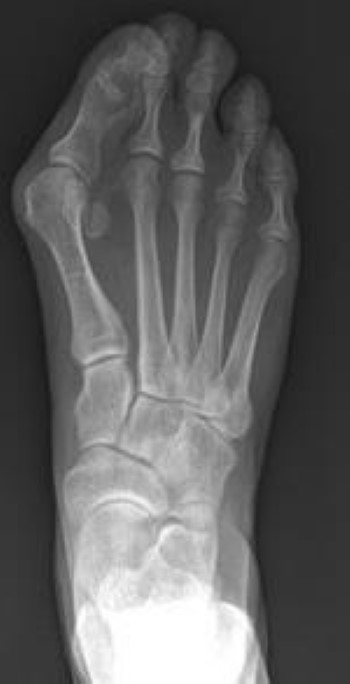

X-Rays

X-rays provide images of bone. An X-ray will allow your doctor to:

• Check the alignment of your toes and look for damage to the MTP joint. The alignment of your foot bones changes when you stand or sit. Your doctor will take an X-ray while you are standing to more clearly see the incorrect alignment of the bones in your foot.

• Determine whether there is arthritis associated with the bunion.

• Determine how severe the bunion is, and how best to correct it.

X-ray of bunion

X-rays of your foot will show your doctor how far out of alignment the bones have become.

Reproduced from Wagner E, Ortiz C: Proximal Oblique Sliding Closing-wedge Osteotomy for Wide-angle Hallux Valgus. Orthopaedic Knowledge Online Journal: Vol 12, No 4, 4/1/2014; Accessed December 4, 2015.